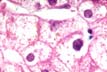

Fig 41 - HEMOSIDERIN

Prussian blue

+ Trivalent iron.

Intralysosomal

In:  Hemochromatosis

& Hemosiderosis.